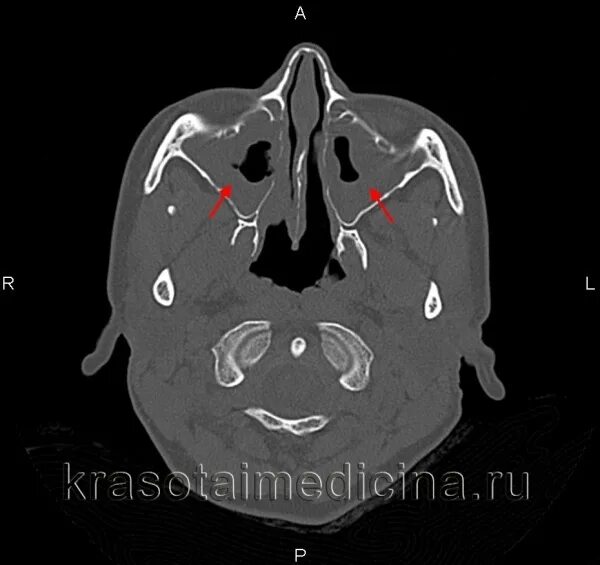

Сфеноидит симптомы у взрослых